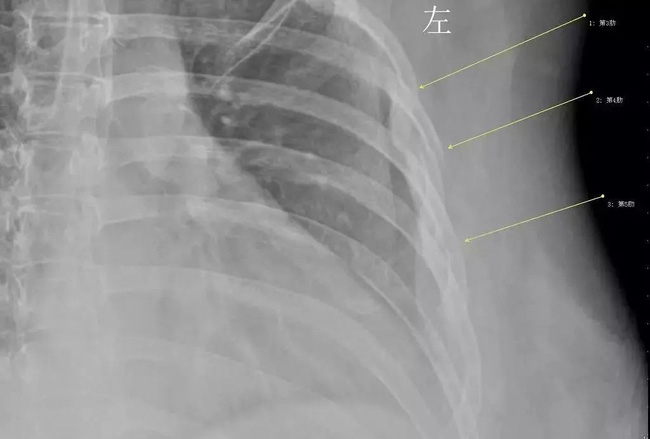

Theo báo cáo, bệnh nhân là Hàn Tiếu năm nay 30 tuổi, cô là nhân viên văn phòng của công ty nước ngoài. Gần đây, đến đợt rét tháng 3, Hàn Tiếu đột nhiên bị cảm lạnh. Sau một trận ho dữ dội, Hàn Tiếu đột nhiên bị khó thở, và đau ở phần ngực. Hàn Tiếu đã đến Khoa phẫu thuật lồng ngực của Bệnh viện trung tâm thành phố Vũ Hán để kiểm tra. Kết quả khiến bác sĩ vô cùng sốc, tất cả xương sườn thứ 3, 4 và 5 của Hàn Tiếu đều bị gãy.